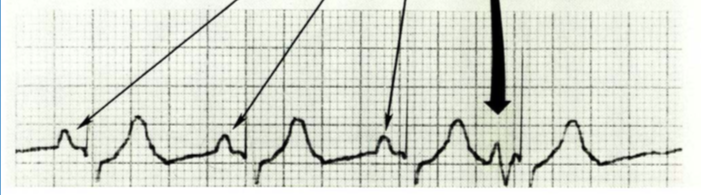

What is V tach? How do we know we are seeing it?

Ventricular Tachycardia (V tach)

↓

3 consecutive PVCs